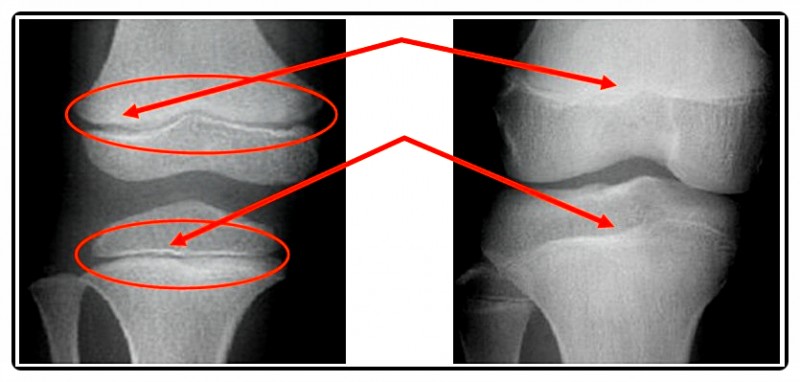

특히 성장판은 균형 잡힌 하중과 자극을 받아야 정상적으로 기능합니다.

하지만 한쪽 어깨가 처져 있거나 다리 길이가 조금이라도 다르면 이야기가 달라집니다.

몸의 무게 중심이 한쪽으로 쏠리면서 특정 성장판은 과도한 압박을 받고,

반대쪽은 자극이 부족해 성장 속도의 차이가 발생하게 되죠.

이런 상태가 지속되면 골반·무릎·척추의 균형이 어긋나면서 성장판이 고르게 자극되지 못합니다.